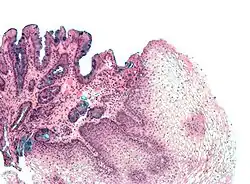

A metaplasia do esôfago de Barrett é bastante visível através da endoscopia digestiva alta. No exame pode ser notada uma lesão de "cor salmão" ou "cor vermelho-róseo". O médico que realiza o exame endoscópico recolhe amostras da lesão esofágica (biópsia).

Estas amostras são analisadas sob microscópio para determinar se as células são de natureza gástrica ou intestinal[5]. A metaplasia intestinal do esôfago de Barrett é geralmente identificada com a ocorrência de células caliciformes no epitélio. A presença das células metaplásicas intestinais é necessária para que o diagnóstico da doença seja confirmado.

Biópsia

O esôfago de Barrett é caracterizado por uma modificação no epitélio do órgão. Na doença, ocorre a presença de epitélio colunar na porção inferior do esôfago, substituindo o epitélio escamoso normal do esôfago. Esta transformação do epitélio é um exemplo de metaplasia. Apesar de o epitélio colunar ser capaz de suportar melhor a ação erosiva das secreções do estômago; esta metaplasia confere um risco aumentado de câncer no esôfago do tipo adenocarcinoma.[6]

As células colunares metaplásicas podem ser de dois tipos: gástricas (similares às do estômago, que não são tecnicamente um esôfago de Barrett) ou intestinais (similares às células dos intestinos). Uma biópsia da área afetada geralmente irá apresentar uma mistura de ambos os tipos. A metaplasia intestinal confere um risco maior de malignidade.